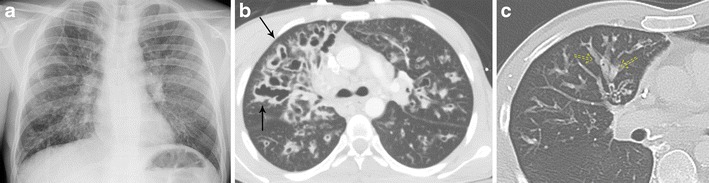

Cystic fibrosis is an autosomal-recessive condition that results in abnormal chloride transport, primarily affecting the lungs and the pancreas. This condition results in viscous secretions that are difficult to clear, leading to decreased mucus clearance of the airways and subsequent airway obstruction, recurrent infections, and airway damage, which progress over time. CT imaging is sensitive to both the early and late stages of cystic fibrosis. Initially, bronchial wall thickening and peribronchial interstitial prominence are seen [24]. As the disease progresses, upper lobe-predominant bronchiectasis develops, increasing in severity over time (Fig. 13a–c) [25]. Mucoid impaction is often present with associated consolidation/atelectasis. Other typical findings include hyperinflation, mosaic attenuation, bronchiolitis, lymphadenopathy, and pulmonary artery enlargement [30, 31]. Symptoms typically present in childhood with recurrent upper respiratory infection, cough, wheezing, and dyspnoea.

Fig. 13.

Bronchiectasis due to cystic fibrosis. a Frontal chest x-ray demonstrating upper lobe prominent course interstitial markings, patchy areas of increased airspace opacity, and bronchiectasis involving the lungs bilaterally. b Axial CT imaging demonstrating upper lobe-predominant cystic and varicoid bronchiectasis and bronchial wall thickening (solid arrow). c Axial CT imaging in another patient demonstrates bronchiectasis and mucoid impaction (dashed arrow) with “finger-in-glove” sign